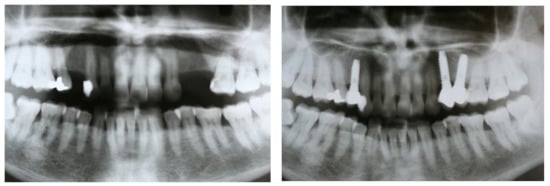

Treatment planning included making diagnostic casts to evaluate intermaxillary relations, clinical photographs, and panoramic radiographs (Figure 1). Most of the patients (especially since 2010) were evaluated with computerized tomography when required.

Figure 1. Panoramic radiographs were taken before treatment as part of the diagnosis and treatment plan and after implant placement and prostheses delivery.